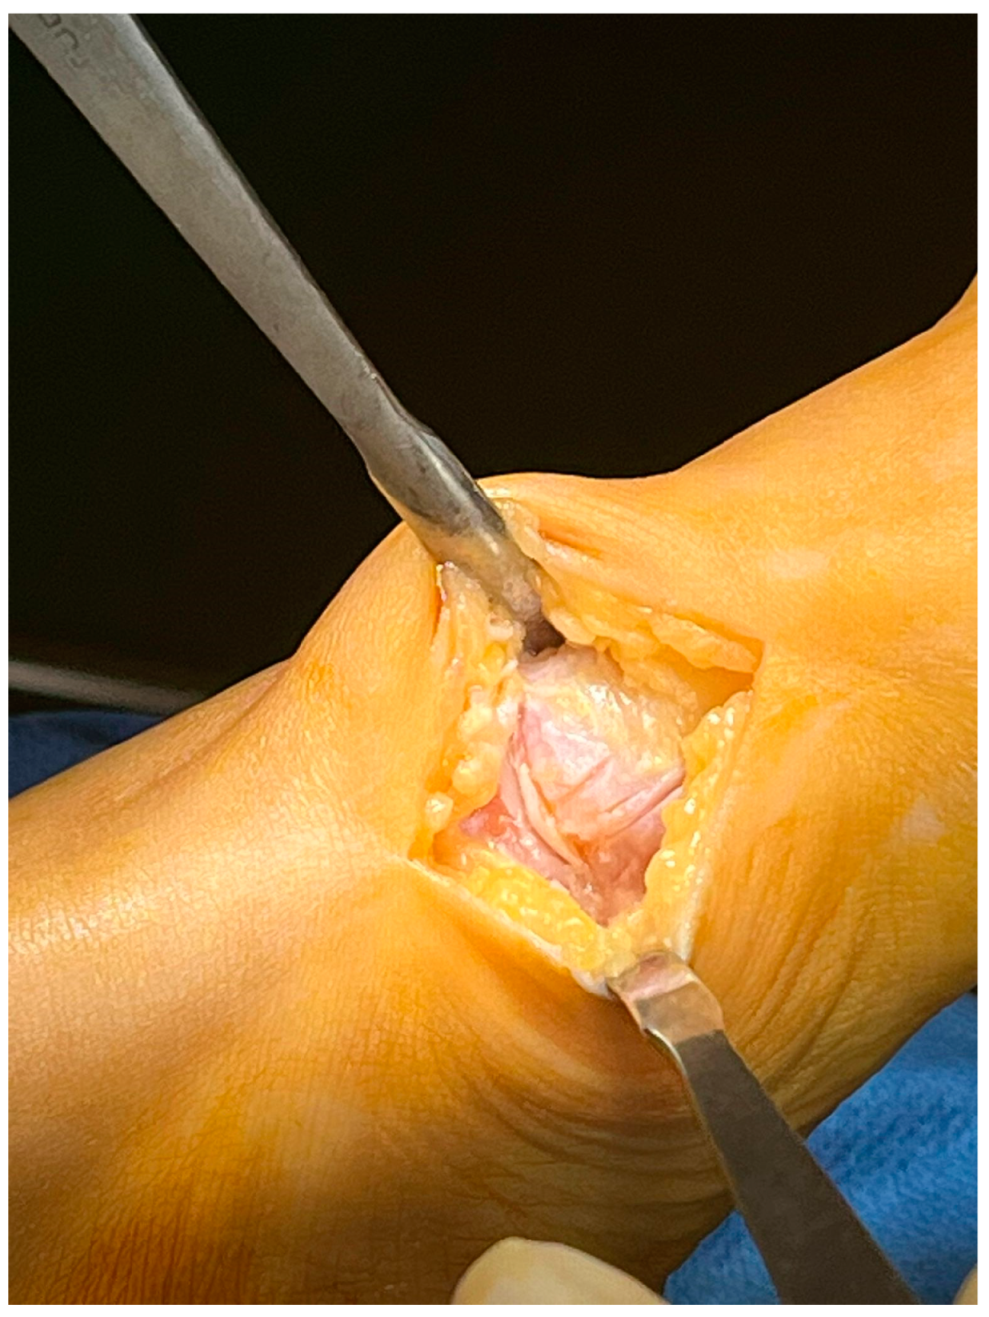

Minimally Invasive Lapidus Arthrodesis Associated with Distal Osteotomy of M1: A Combined Procedure for Hallux Valgus Correction

2. Materials and Methods